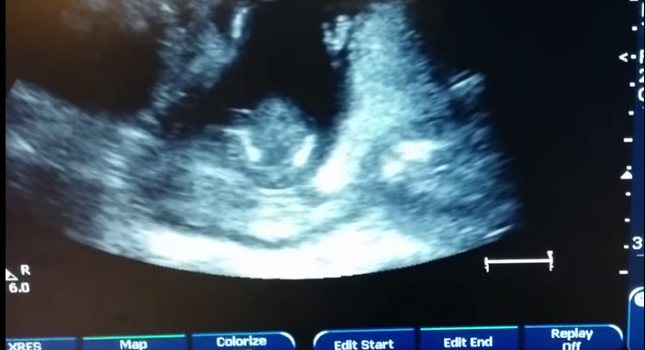

One couple were in for their 14-week baby scan when they noticed their little tyke was clapping along to himself.

Unable to resist the excitement, dad decided to sing along to the claps, making a sweet video of the moment.

Mum Jen Cardinal shared the video on YouTube, writing:

“The experience is one I’ll never forget. The baby clapped three times, then the doctor rewound and scrubbed it while we sang. No mystery. It was amazing.”